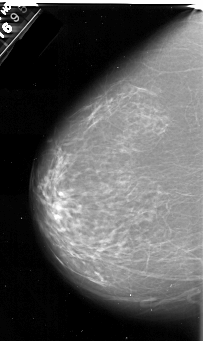

A_1070_1.LEFT_MLO

LEFT_MLO LINES 6961 PIXELS_PER_LINE 3826 BITS_PER_PIXEL 16 RESOLUTION 42 NON_OVERLAY